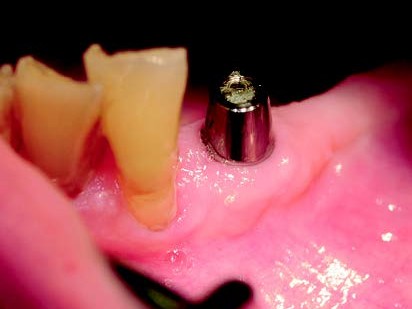

Eine 72-jährige Patientin stellte sich mit einer teleskopierenden Arbeit vor, die seit über zehn Jahren bestand. Der Teleskop-Pfeilerzahn 33 (Abb. 1) war nach Wurzelkanalbehandlung (Abb.2) aufgrund einer rezidivierenden apikalen Ostitis entfernt worden (Abb. 3). Hauszahnärztlich war ein Heil- und Kostenplan mit dem Ziel erstellt worden, sämtliche Unterkieferzähne teleskopierend zu versorgen. Dieser Vorschlag war der Patientin zu invasiv und überstieg vor allem ihre wirtschaftlichen Möglichkeiten als Rentnerin. Der Vorschlag, die bestehende Teleskoparbeit unter Insertion eines Implantates in regio 33 mit der Versorgung über das industriell gefertigte SynCone-Konuskronenprinzip zu erhalten, erschien der Patientin als eine einfache, gute und auch wirtschaftlich für sie realisierbare Alternative sinnvoll. Daraufhin wurde in regio 033 im Rahmen der Spätimplantation ein ANKYLOS C/X-A-Implantat (Durchmesser 3,5 und Länge 14 mm) inseriert (Abb. 4). Nach einer Einheilungsphase von zwei Monaten erfolgte die Implantatfreilegung. Bei der Implantatinsertion zeigte das Implantat einen Osstell-Messwert von 76 ISQ, bei Implantatfreilegung einen ISQ-Messwert von 82. Nach Überprüfung der Parallelität kam ein ANKYLOS SynCone C/ Aufbau 5° der Gingivahöhe 4,5 zur Anwendung. Dieser wurde mit 15 Ncm Drehmoment angezogen. Chairside wurde mit Unterstützung durch den Zahntechnikermeister vor Ort die ANKYLOS Degulor-Konuskappe SynCone 5° mit Retentionen eingearbeitet. Es erfolgten Nachkontrollen halbjährig. Bei der Zweijahres-Nachschau berichtete die Patientin unaufgefordert, dass sie mit der Rettung ihrer schon über zehn Jahren bestehenden Teleskoparbeit die richtige Entscheidung getroffen hatte und dass diese noch bestens in Funktion sei, wie diese selbst demonstrierte (Abb. 5-7).